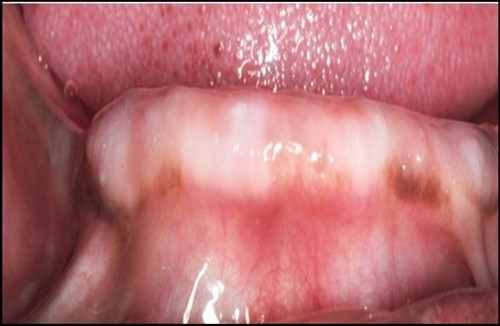

Figure 2.Prpre-operative view of anterior mandibular knife edge ridge.

Post operatively after 3 months, osseointegration was evaluated clinically and radiographically (Figure 5a,b) and the implants were well prepared to receive the prosthesis. The second stage surgery was performed in which cover screws were removed and healing abutment were inserted into the implants (Figure 6). After a time period of two weeks, peri-implant soft tissue healing was examined, and existing denture was relined after relieving at the abutment site. Later, the healing abutment is removed using a 1.25 mm hex driver. Internal portion of the implant is irrigated and dried to make sure if it is free of debris and soft tissue. A periodontal probe was used to measure the gingival cuff height at the right and left canine site of implant location. Selected ball abutment were placed onto each implant using 1.25 mm hex driver and 30 Ncm torque wrench (Figure 7A).